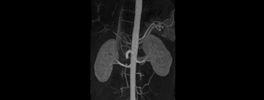

Kidney Angiography